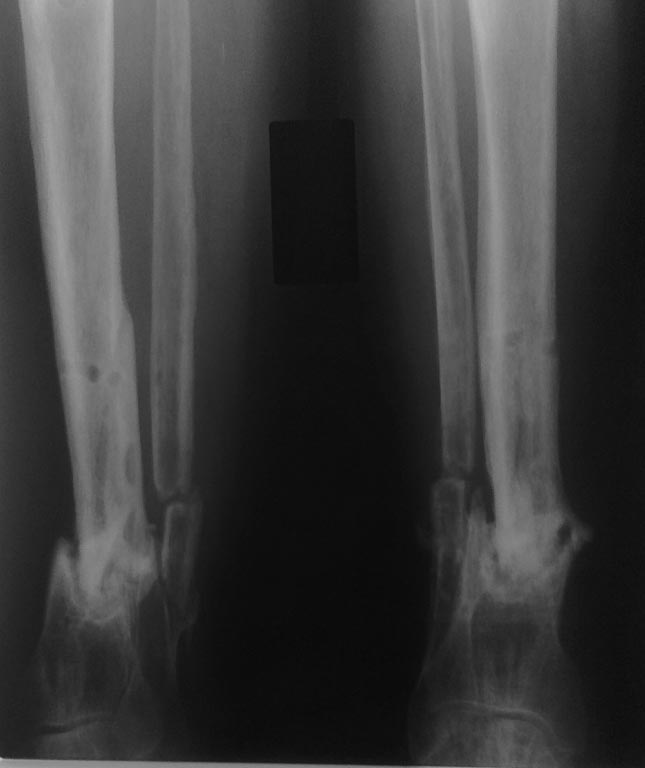

ложный сустав н/3 костей голени |

Больной А 50 лет. Тугой ложный сустав н/3 костей голени, был открытый оскольчатый перелом н/3 костей голени в 2010 году, лечение консервативное, 2011 году по поводу ложного сустава оперирован в г. Ташкенте: ВКДО аппаратом Илизарова, в свизи с болевым синдромом и инфицированием вокруг спиц, больной отказался от аппаратной фиксации, (психологический пациент не совсем адекватный), ч/3 6 мес демонтаж аппарата, но рентгенологических признаков консолидации нет. В данный момент голень фиксирована эластическим бинтом, наступает с помощью троста, хромает, у больного сопутствующий посттравматическая болезнь головного мозга, парез правой в/к. В н/к пареза нет.Какая тактика лучше: 1.У меня на руках есть: Интрамед ретроградный стержень для большеберцовой кости (Chm)- 8-10х240-260мм. и Аппарат Илизарова. 2. Как репонировать костныt отломкb (открытым или закрытым способом), 3. Резекция краев костных отломков (адаптировать) и очистка от рубцовых тканях надо или нет. 4. Аутопластика спонгиозной костью... 5. Оптимальный метод остеосинтеза 6. В проксимальных отделах стержня нет овального отверстия для динамизации, при этой ситуации динамизация...